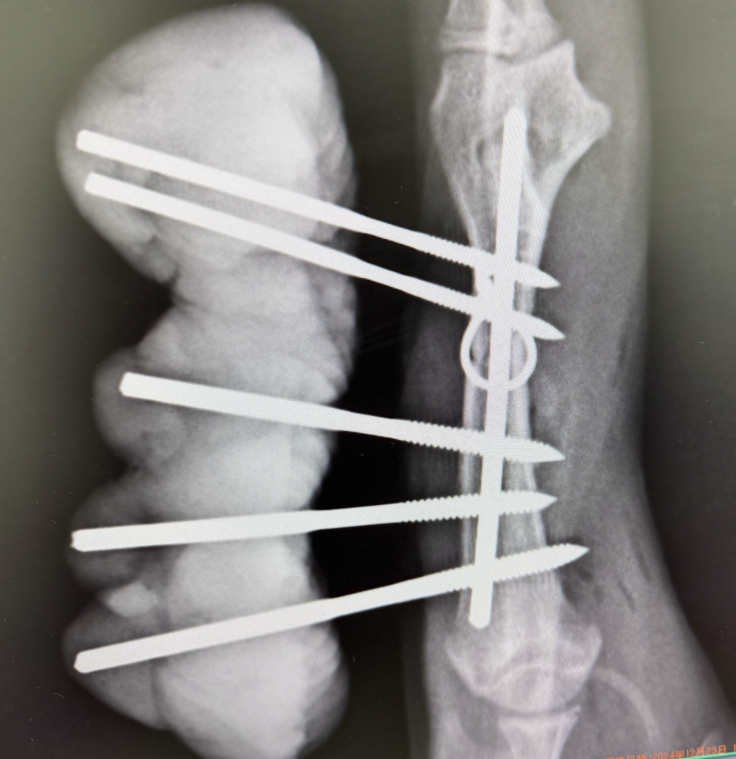

・交通事故で複数箇所骨折した猫、建物火災で全身火傷を負った猫、FIP治療など沢山の猫の治療ができております。